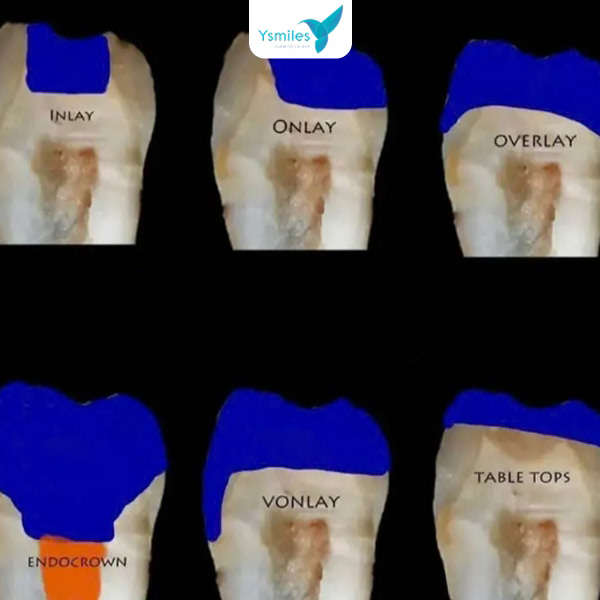

- Vật liệu Sứ (Inlay/Onlay): Với miếng trám bằng sứ, bạn có thể ăn uống ngay vì vật liệu này được chế tạo và nung cứng sẵn, sau đó gắn chặt vào răng bằng chất kết dính chuyên dụng. Tuy nhiên, giá thành vật liệu sứ khá cao nên không phổ biến.

- Vật liệu trám chính hãng: Sử dụng vật liệu Composite nano và Inlay/Onlay sứ cao cấp có độ bền cao, màu sắc tự nhiên như răng thật.